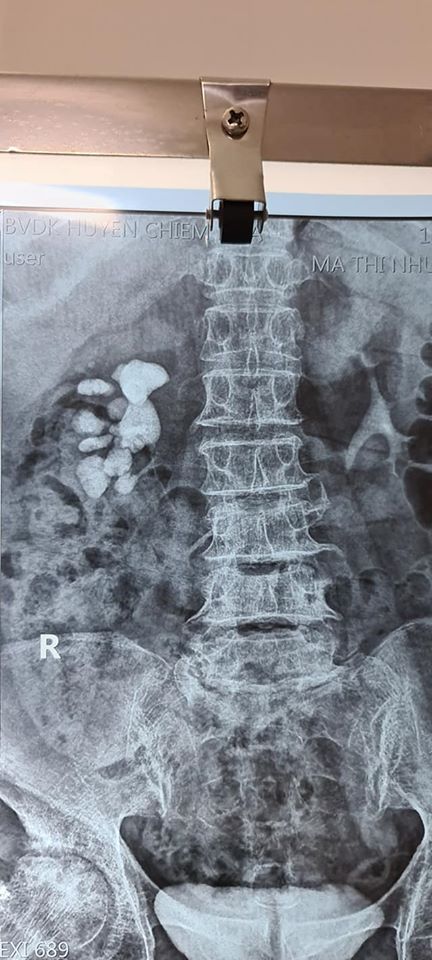

Phẫu thuật hở lấy sỏi thận sỏi niệu quản tại TTYT Chiêm Hóa

Sỏi thận niệu quản là bệnh lý tiết niệu thường gặp nhất, cần phải điều trị sớm nếu không sẽ gây tắc nghẽn làm ảnh hưởng nhanh đến chức năng thận. Hiện nay, mổ mở lấy sỏi thận niệu quản đã được thay thế bằng các phương pháp điều trị khác ít xâm lấn. Tuy nhiên, phẫu thuật mở lấy sỏi vẫn được chỉ định trong những trường hợp sỏi thận phức tạp, sỏi thận niệu quản nhiều vị trí hoặc người bệnh có chống chỉ định thực hiện các phương pháp khác.

Đặc điểm di chuyển của sỏi thận niệu quản trong quá trình phẫu thuật có thể gây biến chứng hoặc sót sỏi sau mổ. Do vậy, sử dụng ống nội soi mềm phối hợp trong mổ là một giải pháp cần thiết để lấy hết sỏi và hạn chế phải mở thêm nhiều đường mổ và tổn thương thêm nhu mô thận.Tuy nhiên, bệnh nhân có hoàn cảnh khó khắn không đủ điều kiện thực hiện các phương pháp tốt nhất như tán sỏi qua da. Vậy nên mổ mở là phương án giúp bệnh nhân được hưởng bảo hiểm xã hội mà không mất thêm chi phí.